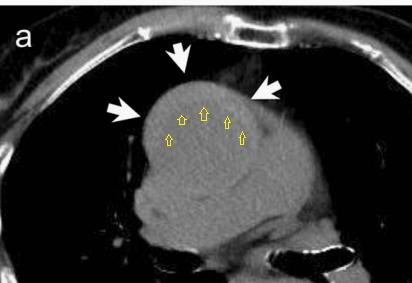

查到一篇文献,作者虽然用箭头标记了,并且是增强CT,但是鲁迅说:我大约肯定没有看出来,这是主动脉夹层!

图21